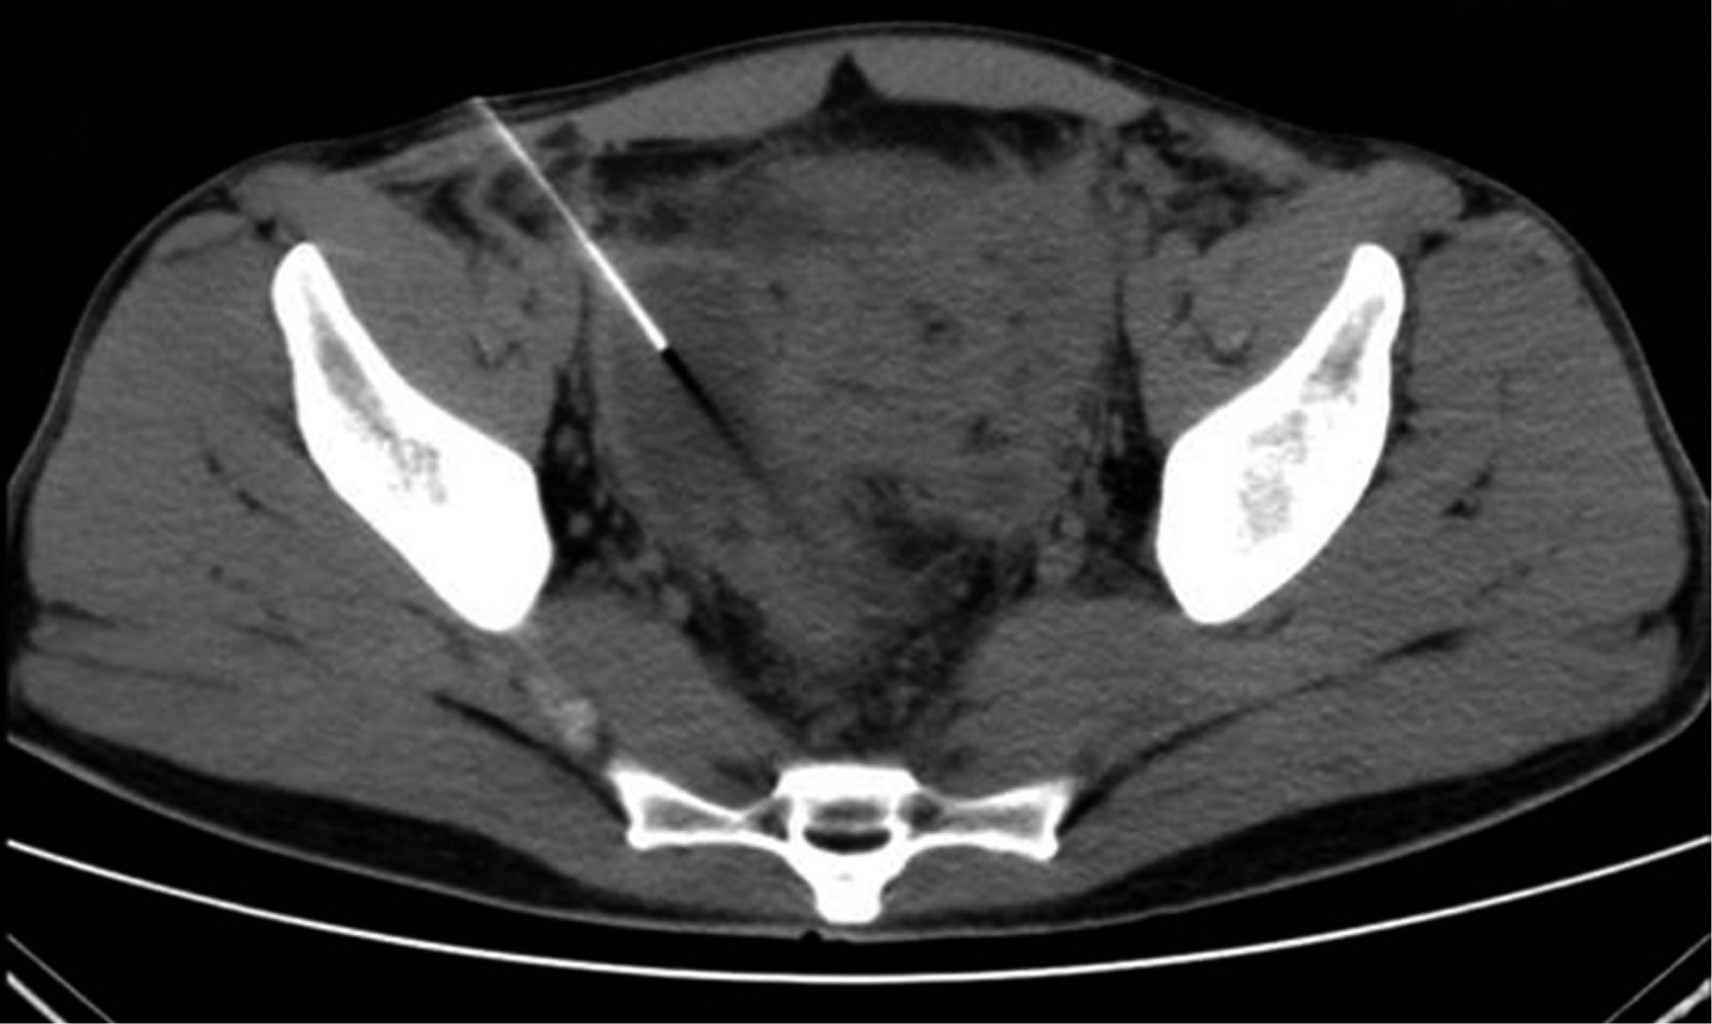

La tomografía de abdomen y pelvis con contraste iv demostró líquido libre en corredera parietocólica derecha, interasa y pericecal. Apéndice cecal con diámetro de 14 mm además de engrosamiento y realce de su pared. Colección supravesical con extensión a fosa iliaca derecha que mide 55 × 75 × 41 mm con un volumen calculado de 88 cm3 (Figura 1) y otra en fondo de saco con extensión a fosa iliaca izquierda que mide 60 × 57 × 70 mm con volumen de 125 cm3. Se decidió punción guiada por ultrasonido con control tomográfico de ambas colecciones (Figura 2), drenando 70 y 120 cm3 purulentos respectivamente. Se dejaron dos drenajes tipo Dawson Mueller® 10.2 fr, uno en fosa iliaca derecha y otro en fondo de saco. Se inició manejo antimicrobiano de amplio espectro con meropenem 1 g iv cada ocho horas y vancomicina 1 g iv cada 12 horas, se dejó en ayuno dos días y se inició apoyo nutricional parenteral durante tres días con oliclinomel®. El cultivo aeróbico desarrolló Streptococcus constellatus sensible a ertapenem, por lo que se cambió cobertura antimicrobiana a base de ertapenem 1 g iv cada 24 horas y vancomicina. El paciente se mantuvo clínicamente estable, sin datos de respuesta inflamatoria sistémica y disminución progresiva del dolor abdominal. Una TAC de control en su tercer día (Figura 3) demostró una disminución importante del líquido en el interior de las colecciones. Se retiró el drenaje derecho en su cuarto día, con un gasto total de 10 cm3; los marcadores inflamatorios presentaron una disminución progresiva durante su estancia, egresándose con 9.9 10^3/μl leucocitos, seg 67%, bandas 0 % y PCR 4.05 mg/dl. Se retiró el drenaje izquierdo previo a su egreso en el noveno día de estancia con un gasto total de 82 cm3. No se realizó apendicectomía de intervalo en el seguimiento debido a que, basado en la edad, los antecedentes y los estudios de imagen al diagnóstico, la probabilidad de neoplasia se consideró baja de acuerdo a las recomendaciones existentes en la literatura.

Figura 3